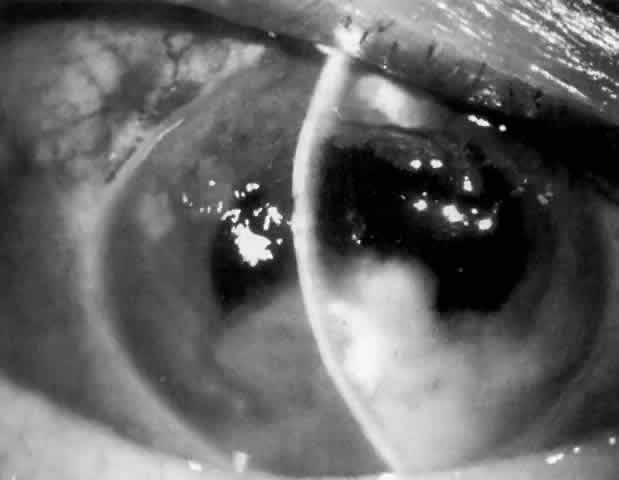

More than a dozen people were blinded after they have undergone cataract surgery in a free eye camp in Kurnool district of Andhra Pradesh. A private organization has conducted this free eye camp where 33 cataract operations were performed. After a month, half of them have lost their sight.

When the victims complained that their eyes started hurting after operation, the organizers of the camp, Nandyal Diocese, asked them to go to various hospitals for check up, later only to inform the victims that they won't get back their vision again. Meanwhile, the State Health ministry has asked for a detailed report from district officials and has promised strict action will be taken.

However, after government interfered, the organizers of the camp, Nandyal Diocese, have suspended the lab technician and agreed to compensate for their alleged medical negligence by bearing further medical expenses of the victims.